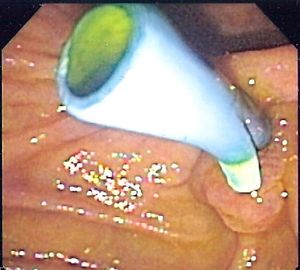

الدعامات الصفراوية، تسمح بتصريف العصارة الصفراوية من المرارة، الپنكرياس، والقنوات الصفراوية إلى الاثنى عشر في حالات مثل التهاب القناة الصفراوية الصاع بسبب الحصوات الصفراوية.

مثال للدعامة الصفراوية.